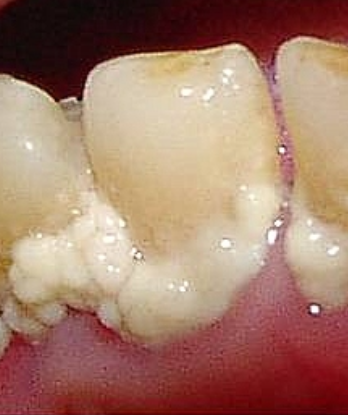

입 속에는 300여 종의 세균이 삽니다. 음식을 먹고 난 후 세균들은 침과 음식물에 섞여서 치아에 붙어 끈끈한 무색의 얇은 막을 만듭니다. 이처럼 세균들이 덩어리져 치아 면에 부착한 얇은 막을 치태라고 합니다.

치아를 제대로 닦지 않고 시간이 지나면 치태가 그대로 굳어져 딱딱한 돌 같은 치석이 됩니다. 치석의 표면에는 세균이 더 쉽게 부착하고 번식하여 잇몸 염증을 일으킵니다.

플라크(plaque)와 치석이 쌓여 잇몸이 치아로부터 떨어지게 되며, 이 틈이 벌어지면서 치주낭이 형성됩니다.